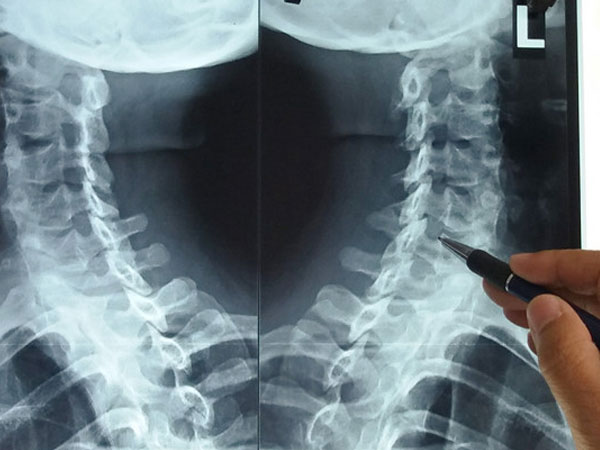

13/11/2017 22:53Dân văn phòng đừng chủ quan khi thoái hóa đốt sống cổ

Nguyễn Thị Quỳnh Thy (30 tuổi, TP. HCM), nhân viên kế toán, thường xuyêncảm thấy mỏi cổ gáy, đau vai và xoay trở khớp cổ rất khó khăn. Nhiều lúc Thy còn bị đau thắt ngực như đau tim. Tuy nhiên, qua thăm khám bác sĩ chẩn đoán cô bị thoái hóa đốt sống cổ.

Bác sĩ Đỗ Tân Khoa, Trưởng khoa Khám bệnh, Bệnh viện Y học cổ truyền TP.HCM, cho biết khoảng 50% bệnh nhân bị thoái hóa đốt sống cổ thường làm nghề kế toán, ngân hàng, văn phòng. Thy là một trong các bệnh nhân rất trẻ mắc căn bệnh này.

Căn bệnh này thường gặp ở độ tuổi trung niên trên 40, song gần đây số lượng bệnh nhân dưới 40 tuổi bắt đầu có xu hướng tăng.

Bác sĩ Khoa cho biết thêm bệnh lý này nặng hơn bởi thần kinh bị chèn ép, khiến bệnh nhân có biểu hiện đau, tê lan xuống bả vai và cánh tay. Dây thần kinh chèn xuống nhánh xương hoành tạo nên những cơn đau thắt ngực khiến nhiều người lầm tưởng là đau tim. Căn bệnh sẽ gây rối loạn giấc ngủ, khi thức giấc rất nặng nề, đôi khi hay quên những việc vừa xảy ra, kém tập trung và đau nửa đầu.

Nguyên nhân dẫn tới thoái hóa đốt sống cổ một phần là lão hóa tự nhiên cơ thể. Song, đa số bệnh nhân đến khám thường do thói quen sinh hoạt tác động lên sụn khớp. Điển hình là tư thế ngồi máy tính không đúng cách, ngủ ngồi, ngửa cổ trên ghế, gập, ngửa cổ nhiều.

Việc điều trị thoái hóa đốt sống cổ rất khó khăn, yêu cầu bệnh nhân phải kiên trì từ 3-6 tháng. Việc sử dụng thuốc tây y chỉ làm giảm những cơn đau tạm thời. Bác sĩ khuyến cáo cần kết hợp liệu pháp điều trị đông y (thuốc, châm cứu, điện châm) và chế độ dinh dưỡng giàu canxi.

Phương pháp mới được nhiều bác sĩ áp dụng để điều trị bệnh này là châm cứu cấy chỉ tự tiêu vào huyệt vị để chống viêm giảm đau, kích thích collagen cho cơ. Đồng thời, bệnh nhân sẽ được kết hợp liệu pháp vật lý trị liệu bằng siêu âm, sóng ngắn, kéo dãn cột sống cổ, giúp phục hồi nhanh